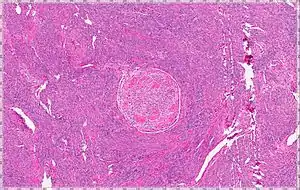

| Intravenous Leiomyoma |

Intravenous leiomyomatosis is a rare condition seen exclusively in women in which leiomyomata, benign smooth muscle tumors, are found in veins. The masses are benign-appearing but can spread throughout the venous system leaving the uterus and even cause death when growing into the heart from the IVC.[1] While the possibility that these arose de novo from the smooth muscle in the blood vessel wall was considered, chromosomal analysis suggests a uterine origin.[2] Intravenous leiomyomata are usually but not always associated with uterine fibroids, and tend to recur.